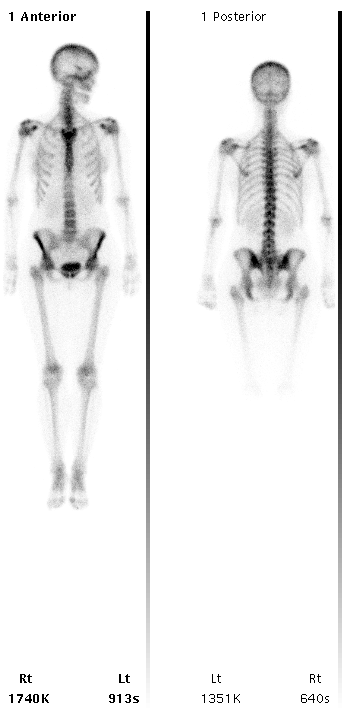

Medicina nucleare scansioni total-body

Le regioni più scure indicano dove si è localizzato il tracciante (Immagini Derrison Hospital)